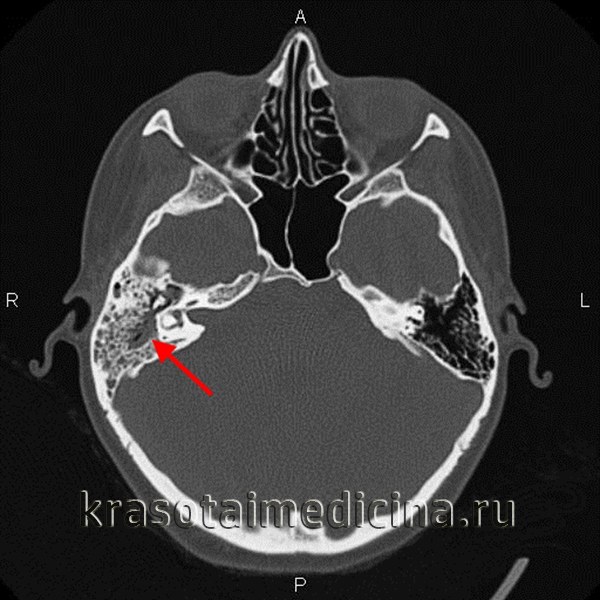

- Комп’ютерної томографії черепа – використовується для перегляду зображення поперечного перерізу по горизонталі і вертикалі. КТ показує детальні зображення будь-якої частини тіла, в тому числі кісток, м’язів, жиру і органів.

Комп’ютерна томографія – стандартний метод, за допомогою якого діагностують мастоїдит. Що це таке? Даний вид діагностики дозволяє чітко розглянути всі структури черепа і оцінити масштаби розвитку гнійних процесів та їх дальність від головного мозку і лицьового нерва.

Ця методика заснована на поетапному дослідженні структури будь-якого об’єкта – порівнюється ефект впливу рентгенівського випромінювання на відмінні по щільності тканини. Отримані дані піддаються складній комп’ютерній обробці.

наприклад, допомагає виявити нечітко помітні перегородки осередків в результаті запального процесу, що явно свідчить про розвиток мастоидита. Крім того, при підозрах на мастоїдит, проводять клінічний аналіз крові і гною з вуха на чутливість до антибіотиків.